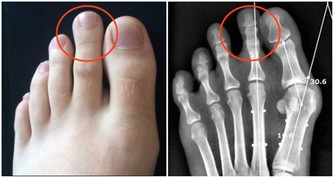

所以有一些骨質疏鬆的病人,或是更年期的婦女,當鈣質需要量增加時,專家就會建議含有草酸的蔬菜要跟牛奶分開食用,但偶爾為之造成的風險其實是不大的。

那麼誰最需要攝取鈣質呢?其實我們每人每天飲食中都要攝取到鈣,但是有些人鈣質攝取需要多增加一點,除了更年期婦女及已經患有骨鬆的人,一定要加倍補充外;另一個需要加倍補充的族群就是9∼18歲成長期的小孩。

以正常攝取量來說,8歲以下的人所攝取的劑量大概是在 700∼800mg,9∼18歲青少年及更年期婦女、骨鬆病人還有孕婦的攝取量,可高達1200∼1300mg,但19∼70歲的成人只要1000mg就好。